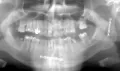

В 2010 году ломал нижнюю челюсть. Срослось нормально, не беспокоила. Недели 3 назад простыл, начало болеть место перелома, немного опухло, болели эубы и сверху и снизу. После того как 7 дней пропил "Цифран СТ" боли прошли, опухоль спала, но остается какая-то скованность в челюсти, рот открывается не полностью. Какие-либо травматические воздействия на челюсть исключены. Что можно сделать для приведения всего в норму и можно ли греть место перелома аппаратом "Алмаг"?